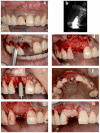

Resorbable Membrane Pouch Technique for Single-Implant Placement in the Esthetic Zone: A Preliminary Technical Case Report

The conventional protocol for lateral guided bone regeneration (GBR) in esthetic areas requires the securing of resorbable collagen membranes using titanium cortical bone pins to immobilize bone grafts. These procedures are highly invasive and can increase patient morbidity and discomfort. Herein, we introduce a minimally invasive novel resorbable membrane pouch technique, wherein collagen membranes can be immobilized by securing them to the periosteum without the need of titanium pins. We describe 11 cases of single-immediate- or delayed-implant placement in the atrophic maxilla esthetic zone. All implants were successful and functional without pain or inflammation and with optimal soft-tissue health and esthetics. Radiographic evaluation with cone-beam computed tomography (CBCT) and esthetic assessment using the pink esthetic score (PES) were performed. At the time of implant placement, the average augmented bone width was 2.8 ± 0.6 mm on CBCT analysis. In all cases, resorption of the augmented bone was confirmed with an average of -1.3 ± 0.8 mm. Soft-tissue outcomes were scored 1 year after permanent restoration. The PES score 1 year after treatment was 11.9 ± 1.4. The resorbable membrane pouch technique with immediate or delayed implant placement for buccal dehiscence in the esthetic area can be predictable and is minimally invasive.